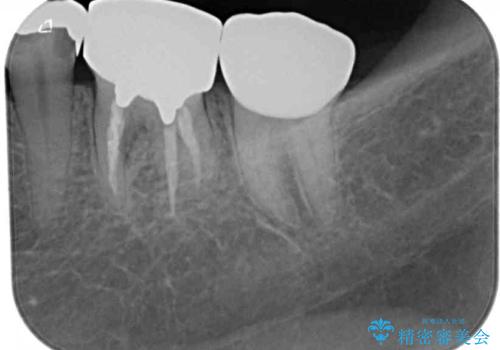

- 銀歯の奥が欠けてしまったとのことで来院された患者様です。

大きな銀歯が装着されており、その下からむし歯が広がっている状態でした。

特に症状はなく、神経組織も健全な状態であったため、むし歯を全て取り切った後にフルジルコニアクラウンにて補綴することとしました。

銀歯などを使用する保険診療は、歯との境界の適合が悪く、むし歯の再発リスクが高いため、長期的な観点から使用は推奨されません。